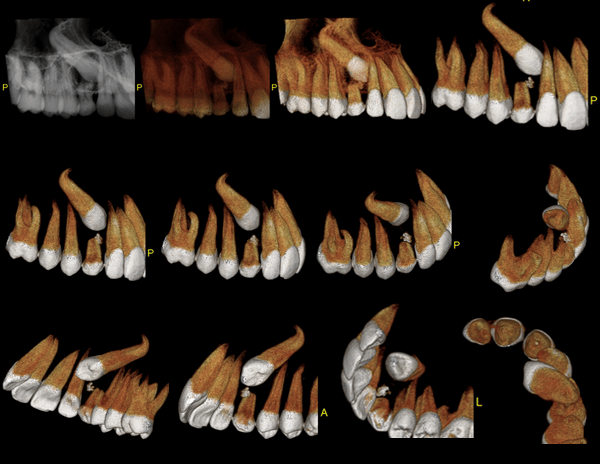

A Tomografia Computadorizada pela técnica do feixe cônico/cone beam (CBCT) introduziu um novo conceito de tomografia computadorizada na região bucomaxilofacial, que por meio da rápida aquisição volumétrica produz imagens com altíssimo grau de definição e fidelidade, além da redução na dose total de radiação emitida ao paciente.

Além disso, ocorre a minimização dos artefatos de imagem em relação à TC médica, o que torna possível a realização de imagens com qualidade diagnóstica e precisão sub-milimétrica, mesmo na presença de estruturas metálicas (restaurações, pinos/núcleos, aparelhos ortodônticos).

CIRURGIA GUIADA

É uma cirurgia realizada apenas com pequenas perfurações no tecido para instalar os implantes. A partir de um planejamento virtual realizado nos softwares específicos, é feita a confecção de guias cirúrgicas (técnica de prototipagem rápida) e, em seguida, há a transferência precisa do posicionamento dos implantes do computador para o paciente.